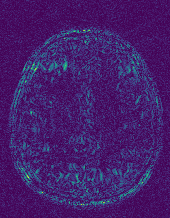

6.2.2 Quality of the Predicted Edges

EPN is utilized to provide edge priors for later reconstruction, so the quality of the predicted edges is very important. In Fig. 10, we provide some qualitative results of the predicted edges of EPN on three multi-coil datasets. Among them, the GT edges are extracted using the Sobel operator. As can be seen from the images, our proposed EPN can predict an approximate contour for the overall subject and can reconstruct accurate edges close to the GT edges under two acceleration factors. This fully verifies the effectiveness and excellence of the proposed EPN.